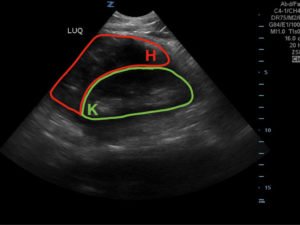

FAST Exam to Diagnose Subcapsular Renal Hematoma

A 49-year-old male presents for evaluation of hematuria and left flank pain after mechanical fall down stairs four days ago. Point-of-care ultrasound (POCUS) focused assessment with sonography in trauma (FAST) exam demonstrated subcapsular renal hematoma. Once a subcapsular hematoma is recognized the provider should keep in mind that this condition may be managed conservatively in patients with two normally functioning kidneys, but may require urgent intervention if the patient is at risk for significant renal disease, such as a single kidney. The use of bedside ultrasound can expedite diagnosis and care for these patients, and allow proper consultants to be contacted early. Some consultants that may need to be consulted include nephrology, urology, and/or internal medicine. This case report emphasizes the utility of the FAST exam for patients presenting for non-acute trauma. The FAST exam can be utilized not only to identify free fluid in the abdomen and pelvis but also to visualize organs and the surrounding tissues for abnormalities after a trauma.